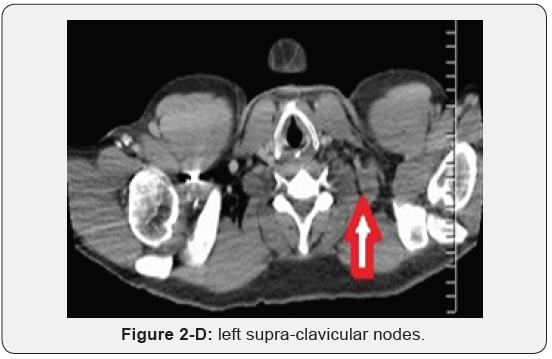

Immunohistochemistry revealed a strong positivity for AE1/ AE3 and Cytokeratin 20 (CK20), and PASD stained for mucin, but the staining for Cytokeratin 7 (CK7), p63, and TTF-1 was negative. The findings suggested a likely primary colorectal origin. He underwent an urgent OGD and full colonoscopy. OGD revealed a normal esophageal mucosa and mild gastritis which tested negative for H. pylori. Full colonoscopy detected a partially-obstructing circumferential mass at the proximal transverse colon near the hepatic flexure. The biopsy report from this colonic mass confirmed an invasive poorly-differentiated colonic adenocarcinoma and the findings were almost identical to the left supraclavicular node’s biopsy. The patient had a computed tomography (CT) scan of the chest, abdomen and pelvis which depicted a locally advanced proximal transverse colon tumor spreading well beyond the serosa posteriorly with local infiltration of pericolic fat and regional lymphadenopathy Figure 2-A. There was a significant metastasis in the para-aortic nodes Figure 2-B, anterior mediastinal nodes Figure 2-C and left supraclavicular nodes Figure 2-D. No evidence of hepatic, pulmonary or bony metastasis noted. Carcinoembryonic antigen (CEA) level was above the normal (22 ng/ml, normal reference <3.5 ng/ml). Alpha-fetoprotein (AFP) level was within the normal ranges.

Nevertheless, MacLoud et al. [16] suggested a retrograde reflux of tumor micro-emboli from the thoracic duct into the Broncho mediastinal trunk through incompetent lymphatics valves and this would possibly explain the anterior mediastinal lymph nodes involvement. Cervical and left supraclavicular lymphadenopathy is well-known to be the first manifestation of colorectal tumors [6,7]. Nevertheless, the occurrence of distant cervical and supraclavicular nodes metastasis without solid organs metastasis is typically rare and was reported only in a few cases in the reviewed literature [6-9]. It has been suggested that after the metastatic involvement of para-aortic lymph nodes, a sequential left supraclavicular metastasis occurs as a result of infiltration of the thoracic duct with tumor cells with formation of skip metastasis between the regional lymph node stations and the distal nodes which are considered as end-nodes of the lymphatic pathway [6].